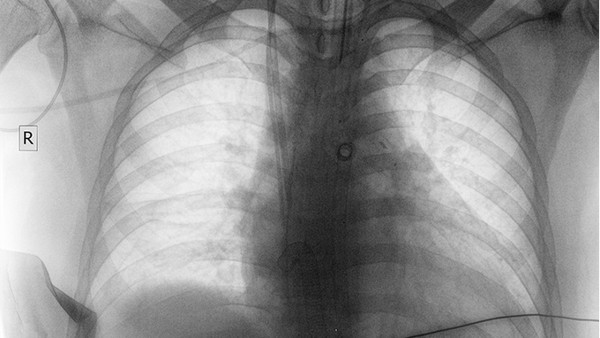

中南大學湘雅醫(yī)院作為湖南省內知名的綜合性三甲醫(yī)院,其呼吸內科和胸外科在肺癌治療領域享有盛譽。醫(yī)院配備了高端的影像診斷設備,如PET-CT和3.0T核磁共振,能夠實現(xiàn)肺癌的早期診斷。在治療方面,醫(yī)院開展了微創(chuàng)手術、射頻消融等技術,同時結合化療、靶向治療和免疫治療等多種手段,為肺癌患者提供全方位的治療服務。醫(yī)院的肺癌診療團隊經(jīng)驗豐富,治果得到廣泛認可。

中南大學湘雅二醫(yī)院在肺癌的綜合治療方面具有較強實力。醫(yī)院呼吸內科和胸外科設備齊全,能夠開展肺癌的各類手術和介入治療。醫(yī)院注重多學科協(xié)作,為肺癌患者制定個性化的治療方案。在肺癌的早期診斷方面,醫(yī)院采用低劑量螺旋CT等技術,提高了早期肺癌的檢出率。此外,醫(yī)院還積極參與肺癌的臨床研究,為患者提供新的治療選擇。